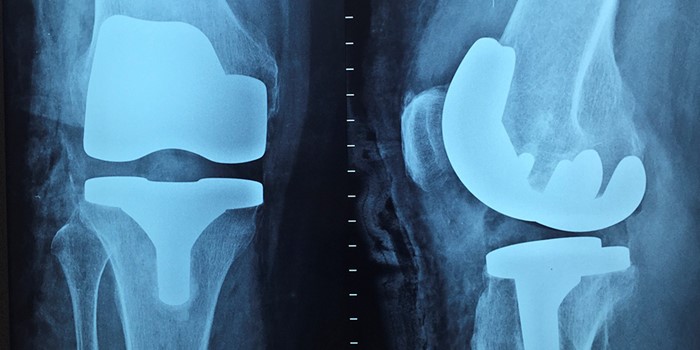

Quando um implante de joelho deve ser feito?

A cirurgia de implante de joelho é necessária quando esse órgão está muito lesionado, o que gera dores muito fortes nos pacientes. Essa condição é comum em casos de pessoas que desenvolveram artrite e suas variações: osteoartrose, reumatoide e artrose pós-traumática.

A primeira decorre do avanço de idade – sendo frequente em pessoas com 50 anos ou mais –, o que pode ser responsável por diminuir a rigidez da cartilagem. A segunda é uma espécie de inflamação na membrana que reveste a articulação, provocando lesões na cartilagem. Já a terceira, refere-se a lesões graves no joelho, como fraturas e rompimentos de ligamentos, o que pode diminuir as funções básicas desse órgão.

O avanço dessas condições leva ao desgaste da superfície dos ossos, os quais, durante o procedimento cirúrgico, são substituídos por revestimentos artificiais. No entanto, mesmo depois de passar por esse processo, a nova superfície também pode se desgastar com movimentos comuns do dia a dia – como andar e correr –, o que leva à necessidade de uma nova cirurgia de substituição da peça implantada. O procedimento costuma ser realizado entre 5 e 10 anos novamente.